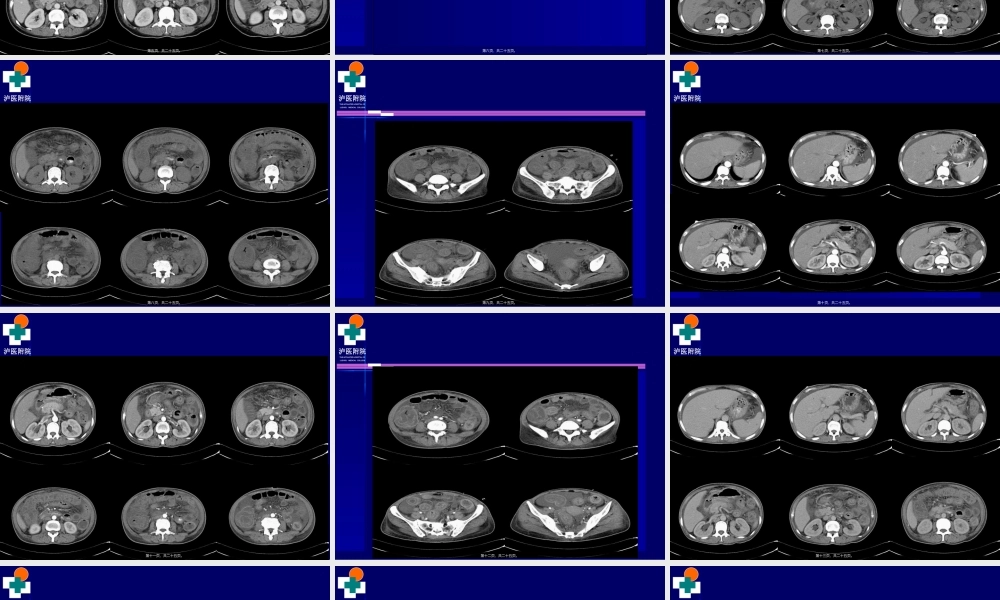

泸医附院THEAFFILIATEDHOSPITALOFLUZHOUMEDICALCOLLEGE院外电解质K+2.06mmol/L胃镜提示:慢性非萎缩性胃炎(wèiyán)伴胆汁反流,胃潴留,动脉血气分析K+<2.0mmol/L,BE-8mmol/L第一页,共二十五页。泸医附院THEAFFILIATEDHOSPITALOFLUZHOUMEDICALCOLLEGE2013/7/19我院腹部CT平扫+增强提示:1、胃壁及所扫肠道壁明显增厚、水肿,以结肠(jiécháng)及空肠明显,肠系膜水肿,腹腔积液。2、肝脏多发小囊肿。脾脏内局限性低密度影,小囊肿?3、目前未见胰腺炎征象。4、胆囊切除。肝内胆管轻度扩张。第二页,共二十五页。泸医附院THEAFFILIATEDHOSPITALOFLUZHOUMEDICALCOLLEGECT平扫第三页,共二十五页。泸医附院THEAFFILIATEDHOSPITALOFLUZHOUMEDICALCOLLEGE动脉(dòngmài)期第四页,共二十五页。泸医附院THEAFFILIATEDHOSPITALOFLUZHOUMEDICALCOLLEGE静脉(jìngmài)期第五页,共二十五页。泸医附院THEAFFILIATEDHOSPITALOFLUZHOUMEDICALCOLLEGE2626//8/20138/2013我院我院CTCT多期增强多期增强(zēngqiáng)(zēngqiáng)扫描扫描第六页,共二十五页。泸医附院THEAFFILIATEDHOSPITALOFLUZHOUMEDICALCOLLEGECT影像(yǐnɡxiànɡ)表现第七页,共二十五页。泸医附院THEAFFILIATEDHOSPITALOFLUZHOUMEDICALCOLLEGE第八页,共二十五页。泸医附院THEAFFILIATEDHOSPITALOFLUZHOUMEDICALCOLLEGE第九页,共二十五页。泸医附院THEAFFILIATEDHOSPITALOFLUZHOUMEDICALCOLLEGE第十页,共二十五页。泸医附院THEAFFILIATEDHOSPITALOFLUZHOUMEDICALCOLLEGE第十一页,共二十五页。泸医附院THEAFFILIATEDHOSPITALOFLUZHOUMEDICALCOLLEGE第十二页,共二十五页。泸医附院THEAFFILIATEDHOSPITALOFLUZHOUMEDICALCOLLEGE第十三页,共二十五页。泸医附院THEAFFILIATEDHOSPITALOFLUZHOUMEDICALCOLLEGE第十四页,共二十五页。泸医附院THEAFFILIATEDHOSPITALOFLUZHOUMEDICALCOLLEGE诊断诊断(zhěnduàn)(zhěnduàn)结果??结果??第十五页,共二十五页。泸医附院THEAFFILIATEDHOSPITALOFLUZHOUMEDICALCOLLEGE肝脏形态大小未见异常,边缘光整,其内密度欠均匀,肝左叶见两枚类圆形低密度影,大者约肝脏形态大小未见异常,边缘光整,其内密度欠均匀,肝左叶见两枚类圆形低密度影,大者约0.6cm0.6cm位于左外叶,无强化。肝内胆管稍扩位于左外叶,无强化。肝内胆管稍扩张,其内未见高密度结石影。胆囊未见显示。脾脏形态大小尚可,脾脏前份见小圆形低密度影,...